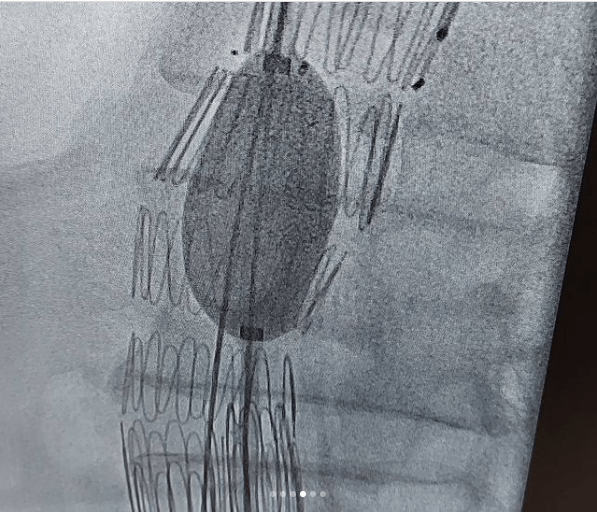

این بیماران با احساس ضربانات مداوم در شکم و درد و گاهاً بدون علامت در معرض خطر پارگی رگ اصلی بدن به نام آئورت ومرگ ناگهانی هستند .دیروز در کمتر از یکساعت بدون جراحی ، استنت هایی که پوشش دیواره ای دارند را مثل لوله داخل ناحیه آنوریسم/یا گشاد شده، تعبیه کردیم و آئورت به سایز نرمال برگشت.